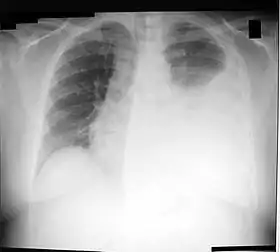

Chest X-ray showing a left-sided pleural effusion (right side of image). This can be treated with thoracentesis.